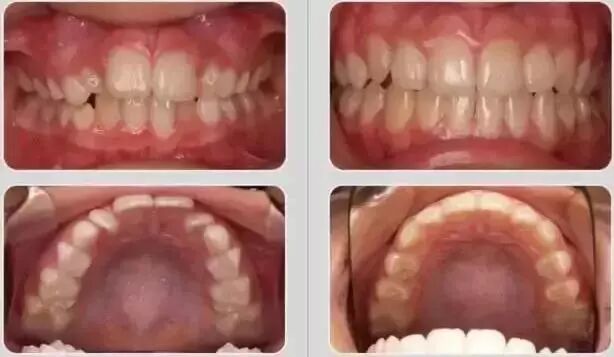

替牙期效果对比